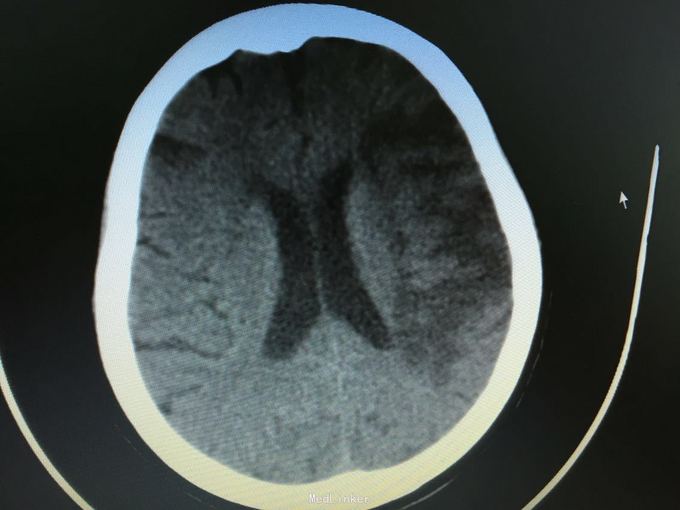

主诉:突发左侧肢体无力伴意识障碍2.5小时。 现病史:患者于2.5小时前突发左侧肢体无力,左侧肢体完全不能动,伴有意识障碍,急诊头CT显示多发脑梗死,为进一步诊治入院。 既往史:高血压,冠心病支架后,阵发房颤。

昏睡,完全混合性失语,双眼向左侧凝视,右侧肢体肌力0级,右侧病理征阳性。 头CT见多发陈旧小梗死。

诊断:大脑半球大面积脑梗死 治疗:抗血小板,脱水,降脂等,抗凝预防下肢静脉血栓

目前住院10余天,意识清楚,但仍遗留左侧肢体肌力0级,混合性失语等严重功能残疾。复查CT显示为左侧大脑半球大面积脑梗死。 讨论:对于高龄,大面积脑梗死患者,时间窗内是否溶栓?静脉还是动脉溶栓?